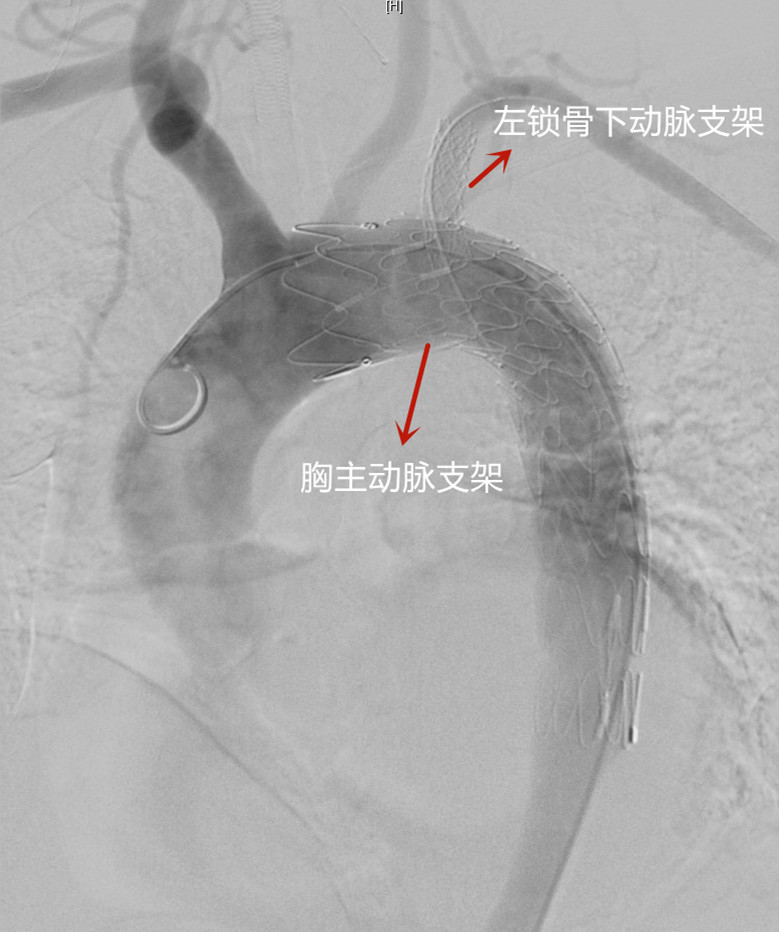

胸主动脉支架、左锁骨下动脉支架植入后造影

术中在透视下,吴巍巍通过精确的定位,仔细沿血管壁送入胸主动脉支架,完全封堵锁骨下动脉及主动脉夹层破口。随后,吴巍巍经左侧肱动脉及锁骨下动脉,采用光纤在主动脉支架开孔并送入导丝,使用球囊扩张后精准植入支架,成功恢复胸主动脉与左锁骨下动脉的血液流通。历时一个半小时,血管外科成功为崔先生解除这颗“不定时炸弹”。术后崔先生恢复良好,精神头也不错,“谢谢大夫们!”崔先生激动地说。